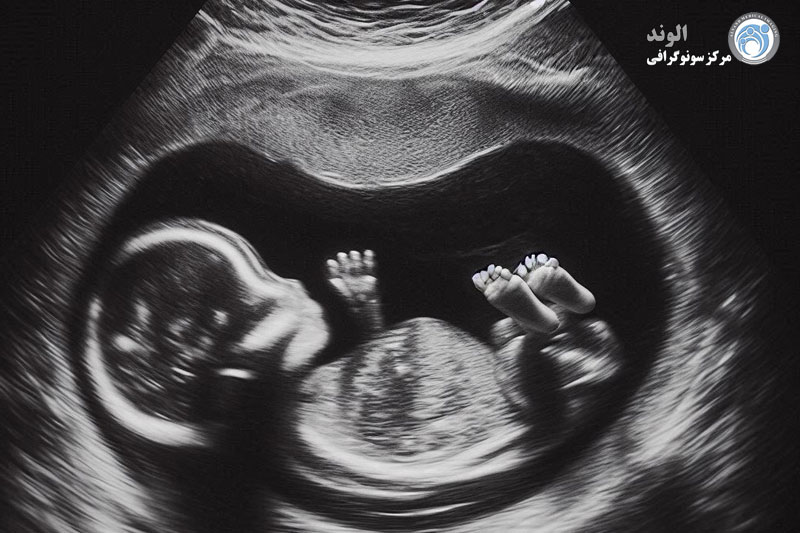

سونوگرافی سه بعدی یا چهار بعدی یک آزمایش انتخابی است که برخی از والدین باردار در دوران بارداری انجام می دهند. تصویر سه بعدی رندر سه بعدی از کودک را نشان می دهد. 4D به یک تصویر متحرک از جنین در رحم اشاره دارد که در طول زمان ضبط شده است. این تست ها به عنوان تست های غیر درمانی شناخته می شوند و تحت پوشش اکثر بیمه نامه های درمانی نیستند.

خود امتحان واقعی معمولا بین 10 تا 45 دقیقه طول می کشد. در طول سونوگرافی، می توانید انتظار داشته باشید که ضربان قلب کودک خود را بشنوید و حرکت کودک را در داخل خود تماشا کنید.

بسته به آنچه که ارائه دهنده مراقبت های بهداشتی در سونوگرافی به دنبال آن است، ممکن است قسمت های مختلف جنین را اندازه گیری کند. پس از آن، میتوانید یک تصویر یا کلیپ ویدیویی از کودک خود ببینید.